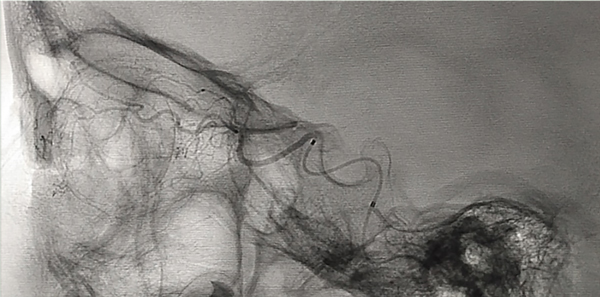

Entre junio 2010 y hasta junio 2021 fueron realizadas 820 sesiones en 176 pacientes (4.6 sesiones por paciente). Todas las intervenciones fueron realizadas por dos neurorradiólogos intervencionistas especialistas. En todos los casos la arteria oftálmica pudo ser cateterizada, 535 directamente (63%) y 285 por vía arteria meníngea media (o meníngea accesoria) con una opacificación coroidea óptima (fig. 1). La principal vía vascular utilizada es la arteria oftálmica con un nacimiento distal al anillo dural (supraclinoidea). De no estar presente o de no poder obtener una correcta opacificación de la coroides por este acceso utilizamos ramos de la arteria carótida externa. La anastomosis entre la arteria meníngea media y la arteria oftálmica está ampliamente descripta en la literatura. Esta comunicación puede darse directamente o a través de la arteria lagrimal o la arteria supraorbitaria. La arteria temporal superficial excepcionalmente puede dar una anastomosis a través de la arteria supratroclear. En nuestra experiencia pudimos corroborar además la existencia de anastomosis entre la arteria meníngea accesoria y la arteria oftálmica, y entre la arteria facial, a través de la arteria angular con la arteria dorsal nasal. La arteria carótida externa es una vía alternativa de gran utilidad ya que presenta múltiples vías de comunicación que pueden ser utilizadas7.

Fig 1: Distribución de las principales vías anatómicas vasculares para quimio-infusión. ACI: Arteria carótida interna. ACE: Arteria carótida externa. El grosor de las flechas es proporcional al orden de frecuencia